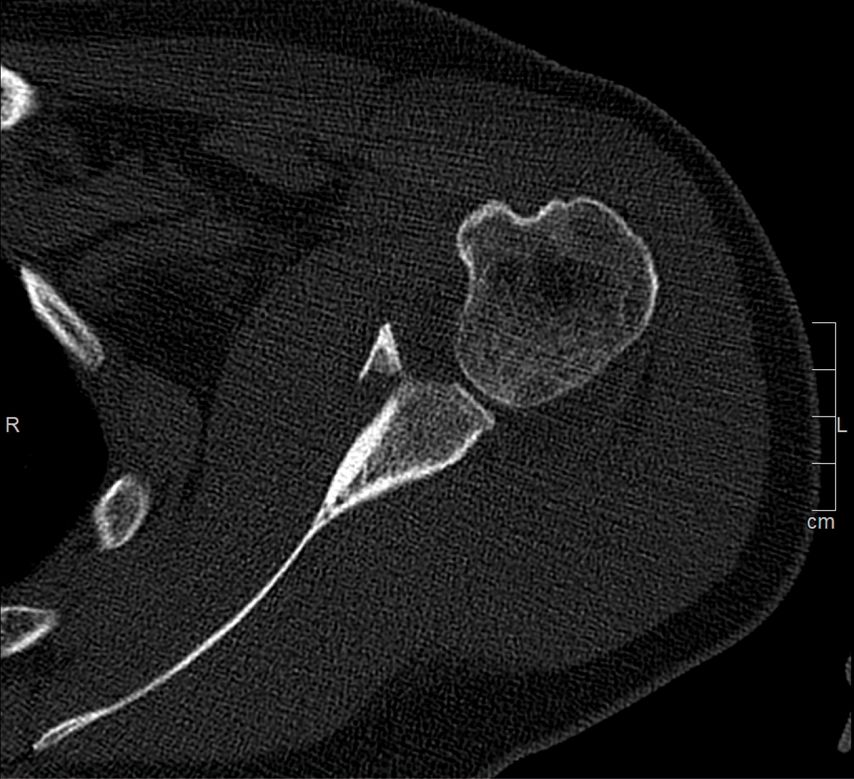

Die operative Versorgung ist indiziert bei instabilen Frakturen mit Subluxation des Humeruskopfes, großem knöchernem Defekt oder erheblichem Stufenversatz. Als Grenzwerte werden in der Literatur häufig eine Fragmentgröße von mehr als 20% der Glenoidfläche sowie ein Stufenversatz von über 5mm genannt (Itoi; Abb. 1 und 2).

Die arthroskopische Refixation hat sich als minimalinvasives Verfahren zur Versorgung selektierter Glenoidfrakturen etabliert. Insbesondere bei Ideberg-Typ-I-Frakturen (Ia ventral, Ib dorsal), knöchernen Bankart-Läsionen sowie kleinen bis mittelgroßen intraartikulären Fragmenten ermöglicht dieses Verfahren eine anatomische Rekonstruktion bei geringer Weichteilmorbidität. Voraussetzung ist das Vorliegen einer akuten Fraktur innerhalb eines Zeitraums von etwa zwei bis drei Wochen nach Trauma. Darüber hinaus müssen die Frakturfragmente reponierbar und von ausreichender Größe für eine stabile Fixation sein, während ausgedehnte Trümmerfrakturen oder eine relevante Schädigung des Skapulahalses ausgeschlossen sein sollten. Relative Kontraindikationen sind ausgeprägte Impressionen, chronische Frakturen mit Fragmentresorption sowie multidirektionale Schulterinstabilitäten. Eine sorgfältige präoperative Planung ist essenziell und basiert auf einer Computertomografie mit dreidimensionaler Rekonstruktion. Diese ermöglicht eine präzise Analyse der Fragmentgröße, der Dislokationsrichtung sowie des prozentualen Defektanteils der Glenoidfläche. Auf dieser Grundlage erfolgt die Festlegung der operativen Strategie, insbesondere die Wahl zwischen Schraubenosteosynthese und Fadenankerrefixation sowie die Planung der Anzahl und Position der arthroskopischen Portale.